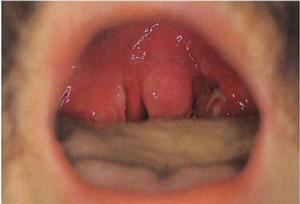

感染髮生後,黏膜急性充血腫脹,粘液腺分泌增多,黏膜表面覆有稠厚粘液。黏膜下血管及粘液腺周圍有淋巴細胞浸潤。咽壁淋巴組織亦充血腫脹,嚴重者可見有白色點狀滲出物。扁桃體充血腫脹,隱窩口內有脫落上皮、細菌及代謝產物和滲出液形成黃白色小點,如融合成片,則形成假膜,炎症侵入扁桃體實質,使整個扁桃體腫大,淋巴濾泡內有化膿現象。頸部淋巴結亦腫大。

鏈球菌起病急,始與上感症狀相似,繼之畏寒高熱,頭痛,全身不適,食欲不振,背及四肢酸痛。咽痛逐漸加劇,隨炎症侵及的部位可引起相應的症狀。咽側束髮炎時引起吞咽困難、疼痛,伴有耳痛,舌根淋巴組織發炎,則有劇烈的灼痛或刺痛,並向兩耳放射。波及咽鼓管時則有耳悶、耳鳴及重聽現象。如病變及侵及喉部,則有咳嗽、聲嘶、呼吸困難等症狀。小兒病情重,可發生驚厥。若伴有咽扁桃體急性感染時,可出現鼻塞,鼻腔及鼻後孔有粘液性分泌物滲出,小兒哺乳困難,易發生嗆咳。檢查見咽黏膜急性充血腫脹,尤以咽側壁及咽齶弓後的黏膜腫脹為重,懸雍垂水腫下垂、鬆弛無力。頸部淋巴結腫大有壓痛,尤以下頜角下淋巴結腫大,觸痛明顯。